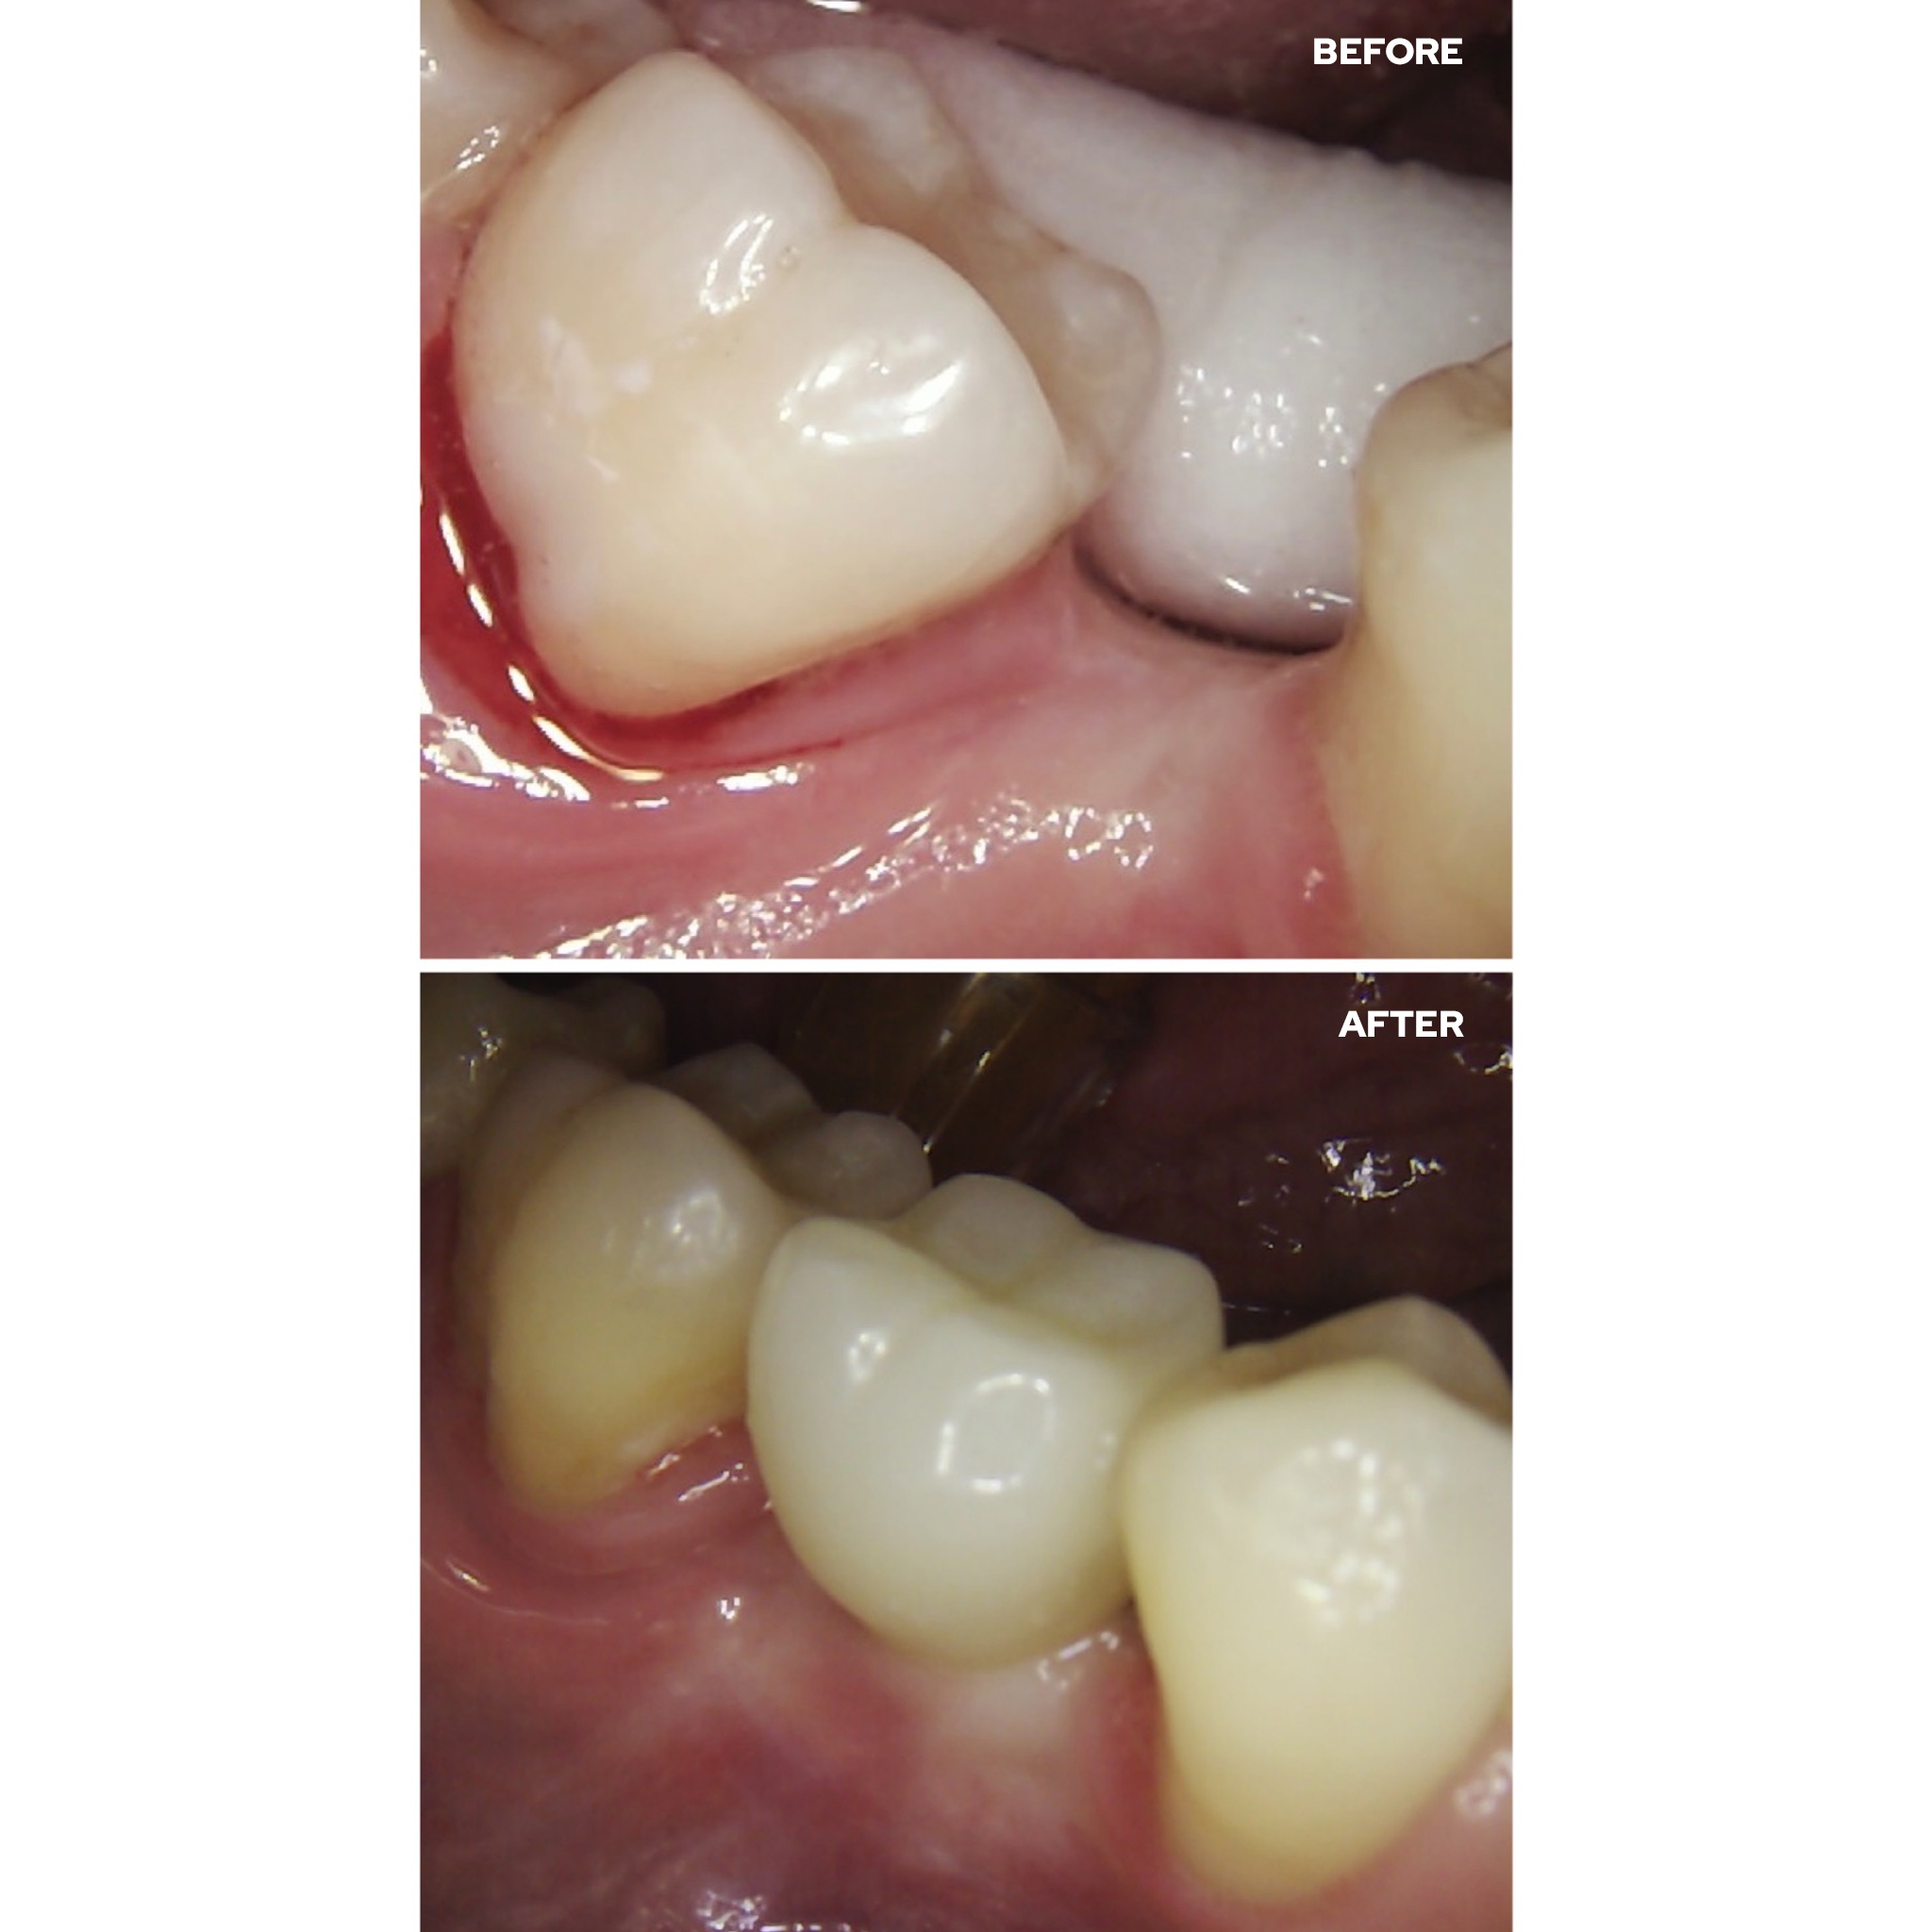

After 6 months of successful

orthodontic treatment, we were finally able to place the implant and the

provisional crown. After 4 months of ingrowth, aligners were removed and a full

ceramic crown was placed. The treatment was successfully completed!✋🏽😉